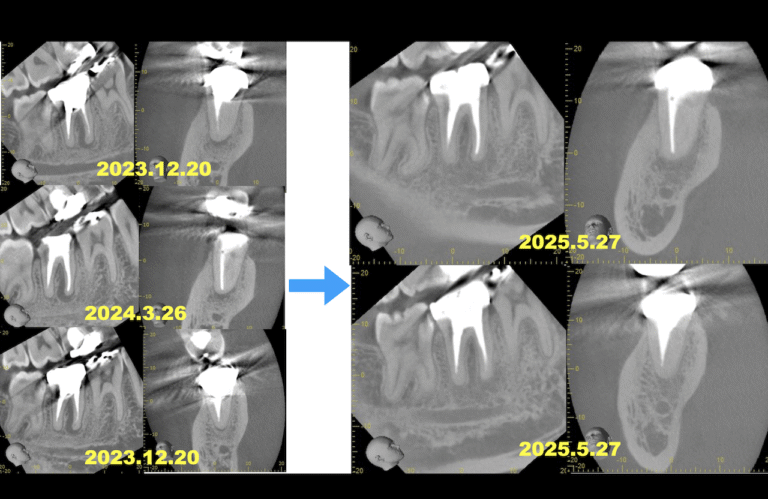

バイト先の治療の経過観察。 Sinus tractがある石灰化が亢進した歯牙の再根管治療〜#31 Re-RCT 1回法 根尖病変が存在していたM根のみ、しかもMLは穿通すらできなかったので手をつけられなかった歯牙の再根管 … 続きを読む Sinus tractがある石灰化が亢進した歯牙の再根管治療〜#31 Re-RCT 1回法 1yr recall